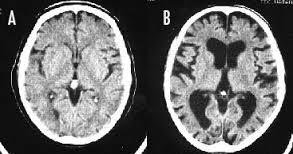

「喫煙者の脳」やはり異変が起きていた ・タバコを吸うと大脳皮質が薄くなる ・タバコを吸うと認知機能が落ちる ※写真は左Aが正常の脳、右Bが喫煙者の脳です。 左の脳と比べて右の脳は隙間だらけになってしまってします。

--- 「喫煙者の脳」やはり異変が起きていた(石田雅彦) - Yahoo!ニュース ---

タバコを吸うと脳がすっきりするのは真っ赤な嘘だ。研究によれば喫煙者の脳では明らかに異常が起きている。認知機能も低下し、大脳皮質が元に戻るのには25年もかかる。一刻も早くタバコなど止めたほうがいい。

>>4049 左が正常で右がヤニカス? 黒い部分は空洞? なんかやばすぎてひく